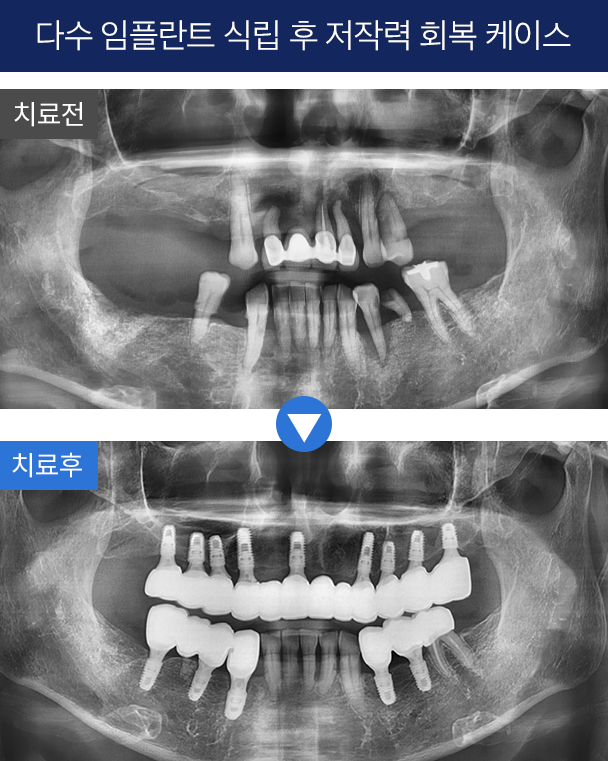

4